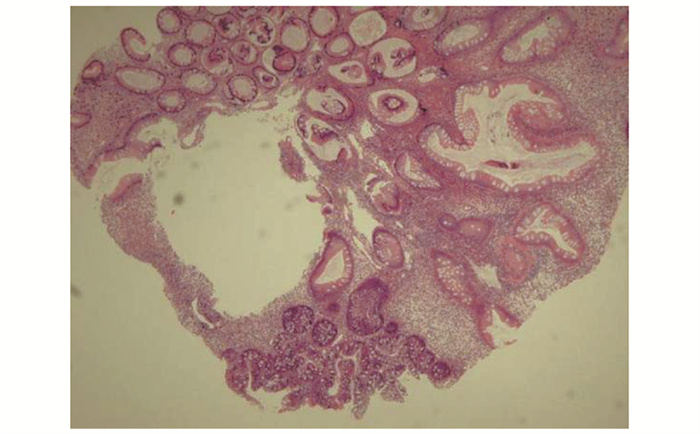

• 摘要: 本文报道Cronkhite-Canada综合征合并无症状新型冠状病毒感染1例。该患者临床表现为食欲减退,毛发及指甲脱落,皮肤色素沉着。内镜检查见胃、十二指肠及结肠黏膜呈弥漫性、大小不一、密集分布的息肉样改变。病程中检出新型冠状病毒核酸阳性。经中等剂量泼尼松治疗后,患者毛发恢复生长,皮肤色素沉着减退。本文总结该患者的诊疗经过并结合文献复习,以期提升临床医生对该病的认知。

Abstract: This article presents a case study of a patient who had Cronkhite-Canada syndrome in combination with an asymptomatic novel coronavirus infection. The patient exhibited clinical symptoms of loss of appetite, hair and nail loss, and skin pigmentation. Digestive endoscopy revealed widespread and varying-sized polypoid changes in the mucosa of the stomach, duodenum, and colon. During the course of the illness, the patient tested positive for novel coronavirus nucleic acid. Treatment with moderate doses of prednisone resulted in the patient's hair regrowth and decreased skin hypopigmentation. The article provides a summary of the patient's diagnosis and treatment and a review of relevant literature, with the aim of enhancing clinicians' understanding of the disease.